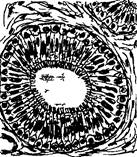

Основой почки является соединительная ткань, Вкоторой расположены многочисленные кровеносное сосуды и система эпителиальных канальцев (нефроны). Каждый нефрон начинается чашеобразной капсулой. Еe внутренний листок тесно прилежит к сосудистому тельцу (Рис. 2).

Каждое такое тельце представляет собой петли анастомозирующих кровеносных капилляров, стенки которых образованы тонким фенестрированным эндотелием. Клетки внутреннего листка капсулы, называемые подоцитами, имеют отростки, контактирующие с базальной мембраной.

В сосудистых клубочках почечных телец в тех местах, куда не могут проникнуть подоциты внутреннего листка капсулы, лежат мезангиальные клетки, которые подобно перицитам имеют отросчатую форму, способны к фагоцитозу и иногда к образованию волокон.

Стенка капилляров клубочка, внутренний листок капсулы и общая для них трехслойная базальная мембрана составляет биологический барьер, через который из крови в полость капсулы фильтруются составные части плазмы крови, образующие первичную мочу. Этот почечный фильтр обладает избирательной проницаемостью, задерживая все то, что больше размеров ячеек в среднем слое базальной мембраны. В норме не проходят форменные элементы крови и некоторые белки плазмы крови с наиболее крупными молекулами. Далее из просвета капсулы почечного тельца первичная моча попадает в проксимальный каналец нефрона, затем в канальцы нисходящей и восходящей части петли Генле, затем в дистальные канальцы, и в собирательных трубках собирается окончательная моча. Состав мочи по мере продвижения по канальцам нефрона изменяется.

Схема нефрона

1 - капсула почечного тельца (Шумлянского-Боумена); 2 - полость капсулы; 3 - наружный листок капсулы; 4 - извитой каналец 1-го порядка (проксимальный каналец); 5 - нисходящая часть петли Генле; 6- восходящая часть петли Генле; 7 - извитой каналец 2-го порядка (дистальный каналец); 8 - собирательная трубочка; 9 - приносящая артериола; 10 - выносящая артериола; 11 - сосудистый клубочек (чудесная сеть).